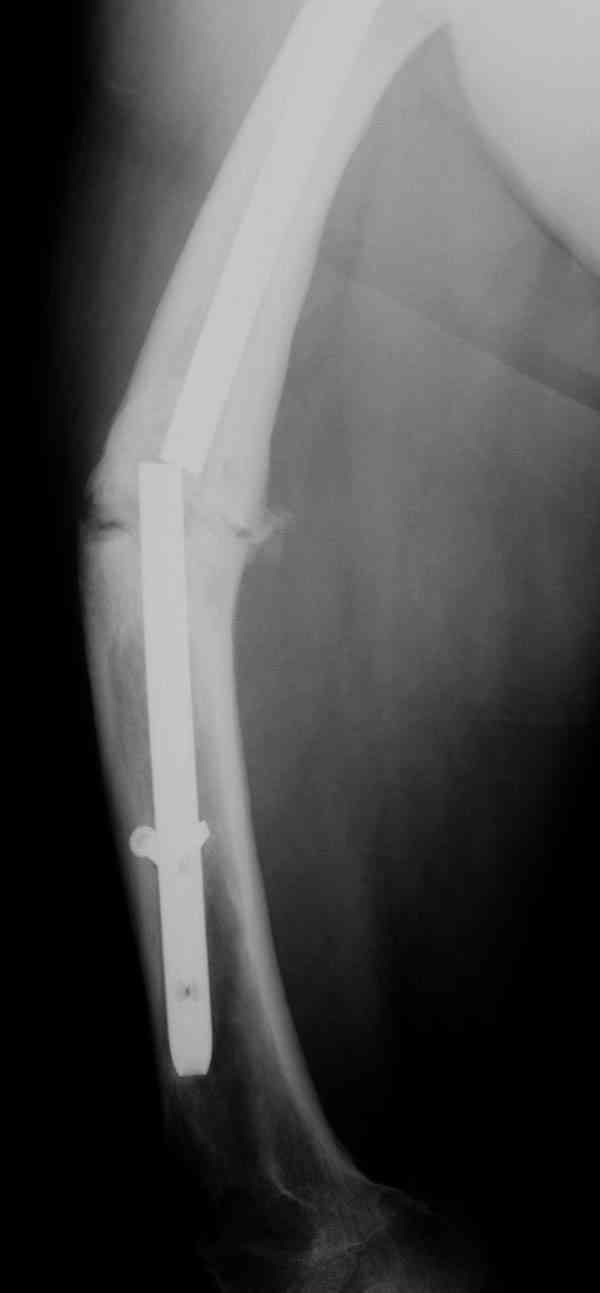

Сросшаяся малоберцовая как распорка привела к образованию ложного сустава. В таких случаях удаляем сломанный штифт и проводим стимуляцию ложного сустава рассверливанием. Рассверливание канала создает стимуляцию на месте ложного сустава, и динамический вариант блокировки штифта с большим диаметром создаст стабильность. Ранняя нагрузка после остеотомии малоберцовой приведет к сращению ложного сустава.